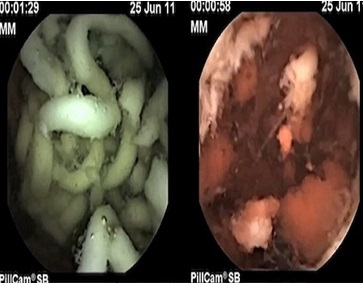

Bằng cuộc thí nghiệm được thực hiện thông qua một máy quay nhỏ, tiến sĩ Kuo đã cho chúng ta thấy một sự thật rằng, những sợi mì ăn liền khi được đưa vào cơ thể con người sẽ không dễ dàng phân hủy sau 2 giờ chúng ta ăn.

Hình ảnh mì ăn liền (trái) vẫn “nguyên hình” sau nhiều giờ nằm trong dạ dày.

Do vậy, mì ăn liền được cho là một đối thủ đối với hệ tiêu hóa của chúng ta, khiến chúng phải làm việc và hoạt động nhiều hơn để tiêu hóa. Điều này hoàn toàn khác khi chúng ta ăn các loại mì tự làm khác.